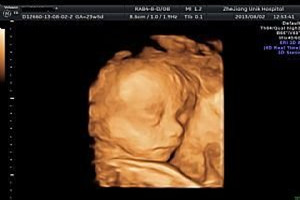

很多第一次做四维彩超检查的准妈妈们都有些紧张和担心,其实做四维彩超检查前不需要什么特殊的准备,但一定要在合适的时间做四维彩超,胎儿在孕20周以后肢体及各主要脏器已经全部发育,但在孕22~28周因胎儿器官发育更加完善,而且羊水量较多,适合做胎儿畸形筛查。那么女人四维彩超检查前要注意什么?

2、胎儿在孕20周后肢体及各首要脏器已经悉数发育,怀孕后四维彩超的查看时间是22周--28周,比较适合的查看时间是24周--26周,具体查看时间还需依据胎儿发育大小以及孕妈妈羊水多少决定。并且羊水量较多,适合做胎儿畸形筛查,这是四维彩超前注意事项。